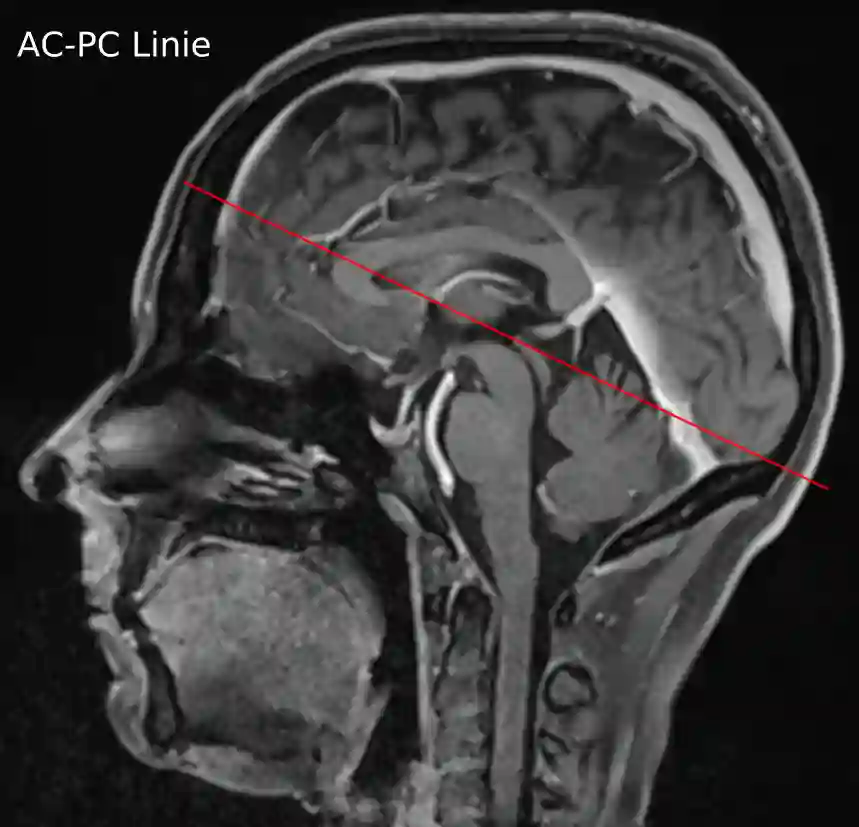

AC PC Linie im sagittalen MRi

Darstellung der AC-PC Linie als rote Linie im sagittalen MRI einer T1 Kontrastmittelsequenz.